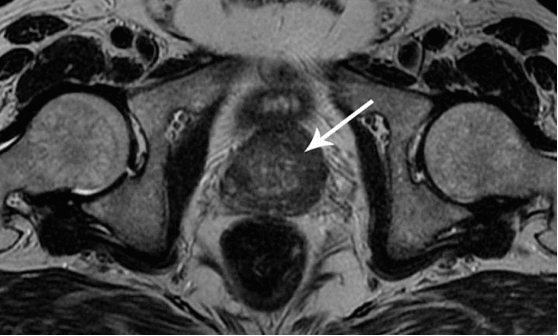

Quiero mostrar algunas fotos de lo que sucede con el sistema genitourinario y otros órganos internos de un hombre cuando deja de tener sexo.

Debido a la congestión, aparecen depósitos de colesterol en los vasos que pueden formar coágulos de sangre. Un coágulo de sangre supone una alta probabilidad de infarto o accidente cerebrovascular. Fue el infarto el que mató al hombre cuyo corazón se puede ver en la foto.